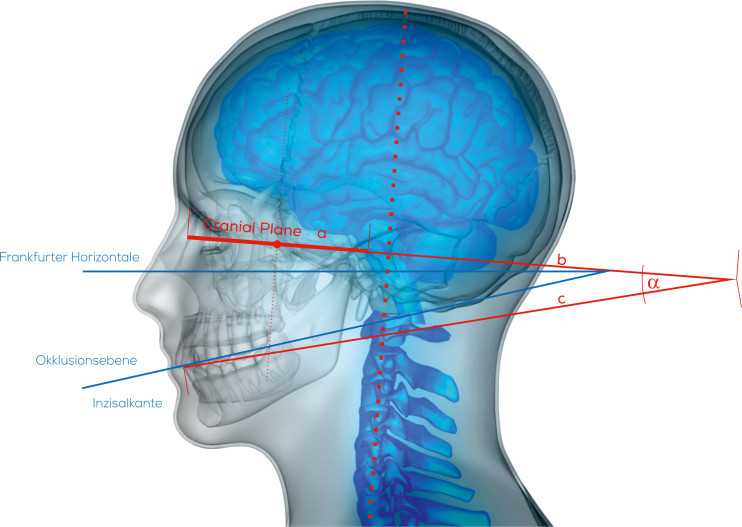

Der zentrale Punkt, von dem die Messungen ausgehen, ist die Mitte zwischen rechtem und linkem Gleichgewichtsorgan. Bei unserer ersten Definition des Mittelpunktes sind wir (2016) von der Mitte des Abstandes der beiden Inci vestibulari ausgegangen, da dieser im DVT mittlerer Auflösung leicht zu bestimmen ist (Abb. 21).

Exakter ist jedoch die Bestimmung des zentralen Wahrnehmungs­ortes des Gleichgewichtsorgans, der Macula sacculi. Diese befindet sich im Sacculus vestibularis der jeweiligen Seite. Die Mitte der Linie zwischen dem Sacculus vestibularis dexter und sinister ist dann der ursprüngliche Nullpunkt der CranioPlan-Analyse. Dieser Punkt liegt etwas posterior zur Mitte der Hammerknöchelchen und gibt den exakten OriginPoint (O-Punkt) als Ausgangspunkt der afferenten Sym­metrieachse an (Abb. 22–24).

Die zu bildende Fläche (CranioPlan) wird nun auf den Mittelpunkt der Bipupillarlinie zentriert. Verlängert man diese Fläche um das Drei­fache nach dorsal und verbindet das hintere Ende mit der Okklusionsebene, so erhält man einen Winkel, der dem Winkel der Frankfurter Horizontale (Orbitalpunkt/Tragionslinie) mit der Okklusionsebene entspricht. Da diese Grundlinie der Frankfurter Horizontalen nicht so genau bestimmt werden kann, sind die Bezugswerte der CranioPlan-Analyse wesentlich genauer und auch leichter reproduzierbar (Abb. 25).

Nach Lehmann et al. beträgt der Winkel der Frankfurter Horizontalen zur Camperschen Ebene (früher gleichgesetzt mit der Okklusionsebene) 10°bis 15°. Vertikale Gesichtstypen und flache asiatische Schädelformen haben einen höheren Wert, horizontale Gesichtstypen einen eher flacheren Winkel. Nach Untersuchungen von Slavicek 1984 beträgt die Abweichung der Camperschen Ebene von der Okklusionsebene nach dorsal jedoch ca. 8°. Das heißt bei genauerer Betrachtung müsste man einen Winkel von 2° bis 7° zwischen CranioPlan-Ebene und Okklusionsebene mit einer Streuung von ca. 6° als Normwert bezeichnen.

Im Idealfall wäre dann bei der vorgestellten Patientin ein Wert von 13° als vertikaler Typ noch akzeptabel (Abb. 26). Vor der bimaxillären Umstellungsosteotomie kippt die Okklusionsebene nach links cranial (Abb. 27a+b).